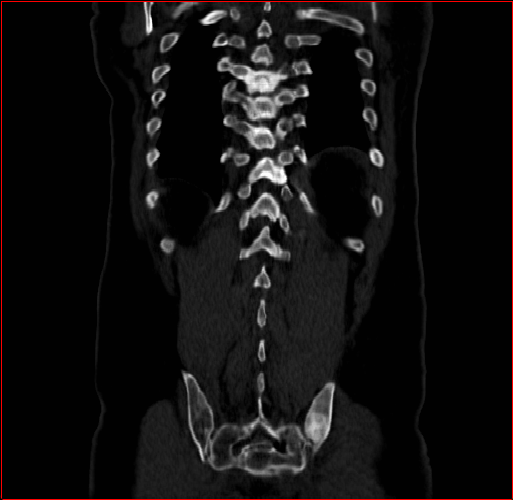

Figure 4 shows qualitatve results of MAISI-v2 ControlNet for different body regions and voxel sizes.

Head Region

1.1×1.1×1.11.1\times 1.1\times 1.1

mm

256×256×256256\times 256\times 256

Chest Region

1×1×11\times 1\times 1

384×384×384384\times 384\times 384

Abdomen Region

1×1×0.71\times 1\times 0.7

512×512×768512\times 512\times 768

Refer to caption

Figure 4: MAISI-v2 segmentation-guided results for small to large volume size and three different regions.